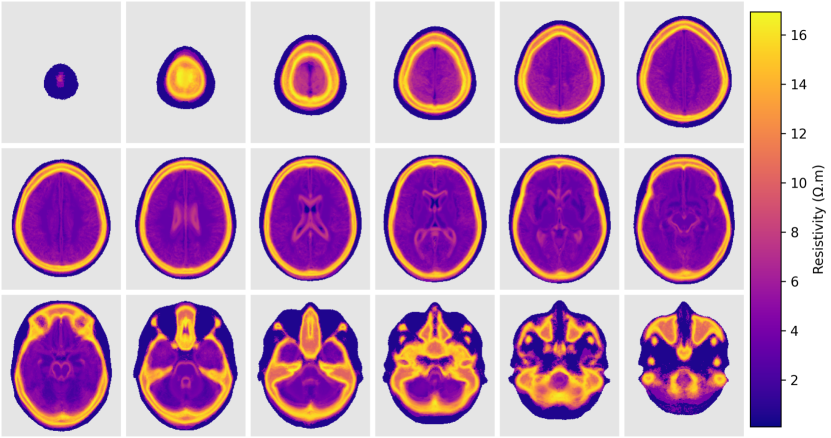

The static component of the atlas at 1 kHztimes1kilohertz1\text{\,}\mathrm{kHz} is presented in Figure 6. The figure shows transversal slices of the average (Figure 6(a)) and standard deviation (Figure 6(b)). It is possible to see high resistivity regions in the forehead, caused by the thick bone and the frontal sinus, in the zygomatic bones and the petrous part of the temporal bone in the base of the skull.

Figure 6: Transversal slices of the static component of the atlas (resistivity) at 1 kHztimes1kilohertz1\text{\,}\mathrm{kHz}. (a) average; (b) standard deviation.

Figure 7 shows slices of the atlas built in terms of conductivity, resistivity, and relative permittivity and in different frequencies. The figure shows that the average resistivity and permittivity decrease with increases in frequency while conductivity increases. Although the average process tends to eliminate small features of the images, it is still possible to see small and thin structures inside the brain, like the longitudinal fissure, third and fourth ventricles and central canal.

Figure 7: Statistics of the atlas in different frequencies. (a) average; (b) standard deviation.